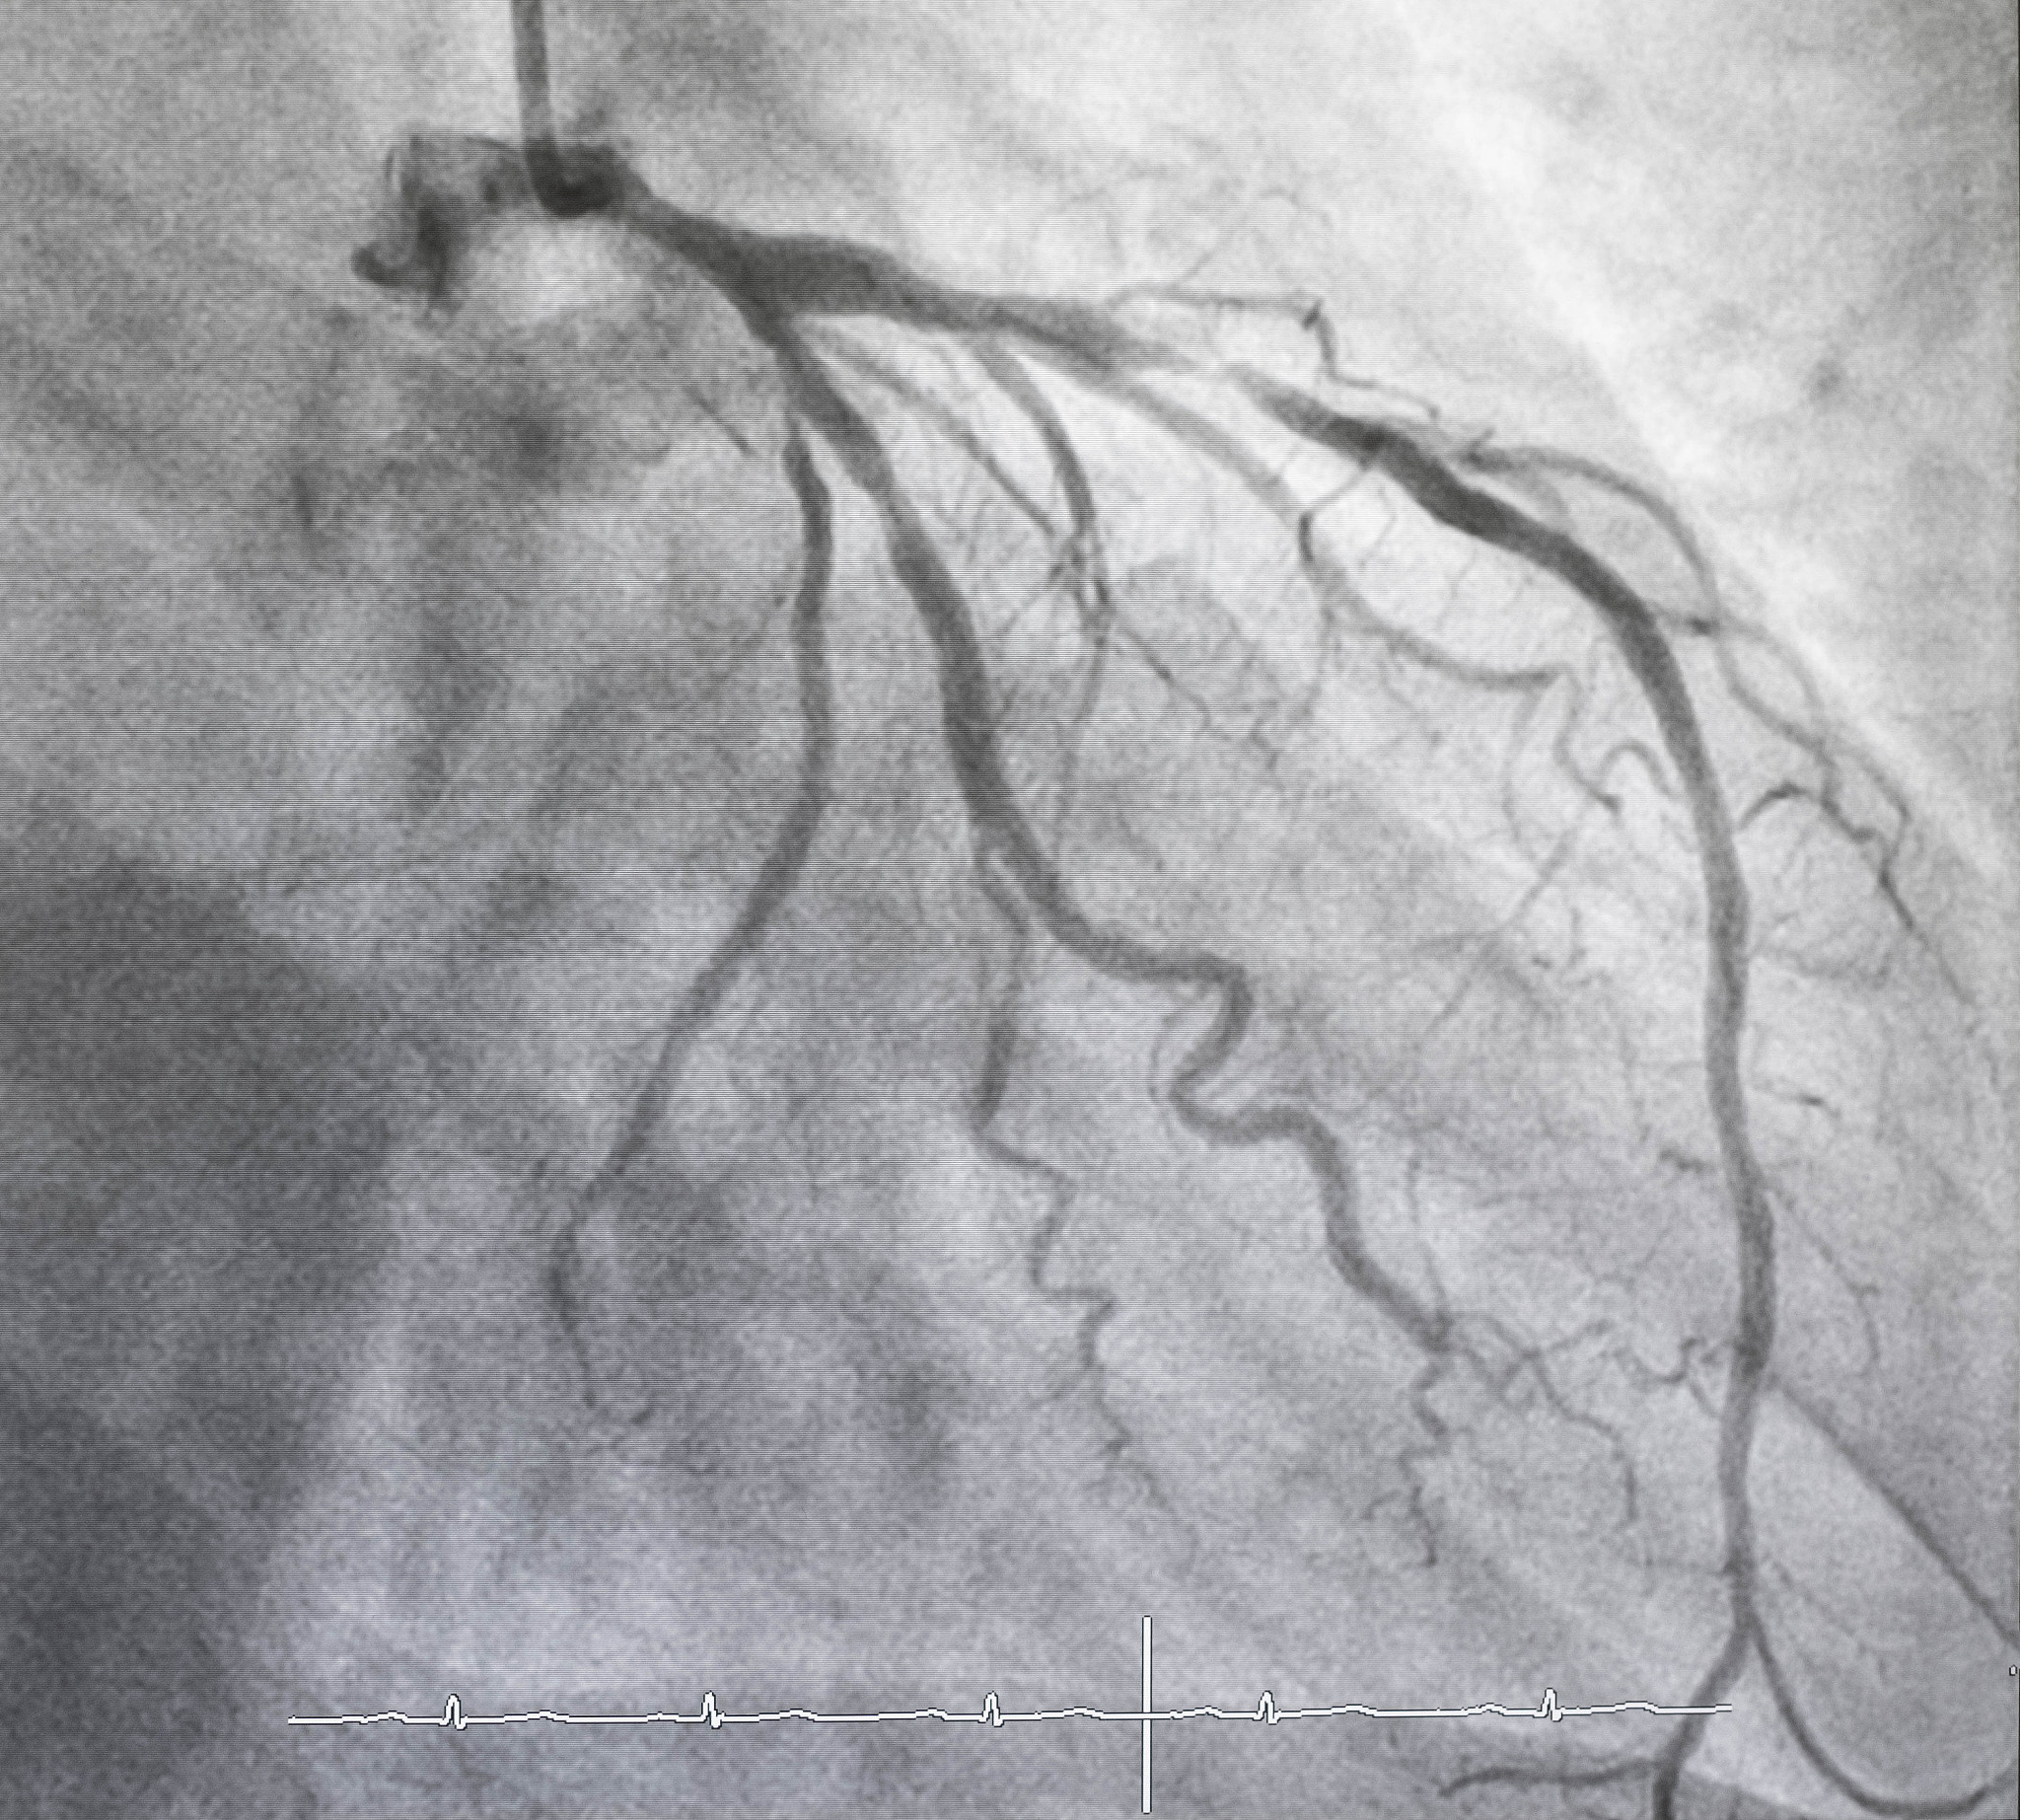

颈动脉超声造影(Carotid CEUS)是一种推荐的诊断方法,由于其操作简单便捷、实时监测、非侵入性、无辐射暴露、非肾毒性和床边检查的特点,在临床应用中备受青睐。